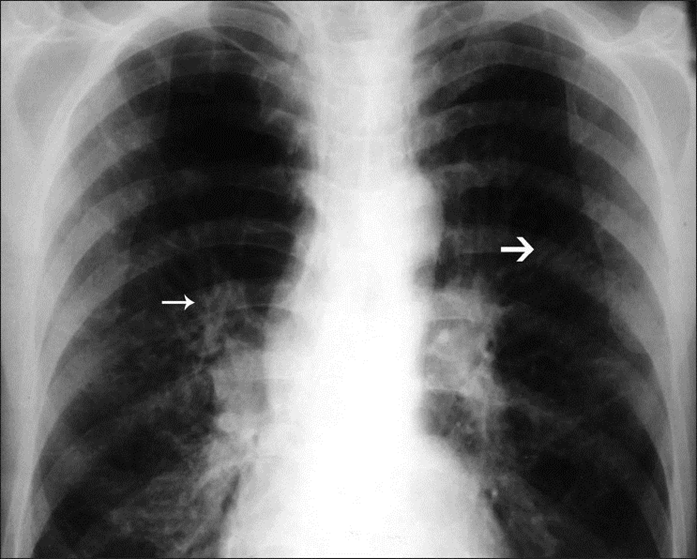

- Rg грудной клетки: симптом «трамвайных рельсов» (см. рис.1), симптом зубной пасты (дают тени от не откашлянной мокроты и исчезают, когда мокрота откашливается), наличие полостей (в 84% случаев Rg может быть нормальной у пациентов с бронхоэктазами, определимыми на КТ)

Рис 1. (симптом трамвайных рельсов по толстой стрелке, симптом «зубной пасты» по тонкой стрелке)